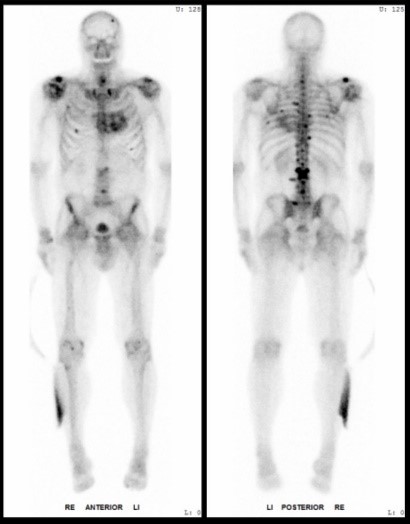

Bildergalerie (5 Bilder)